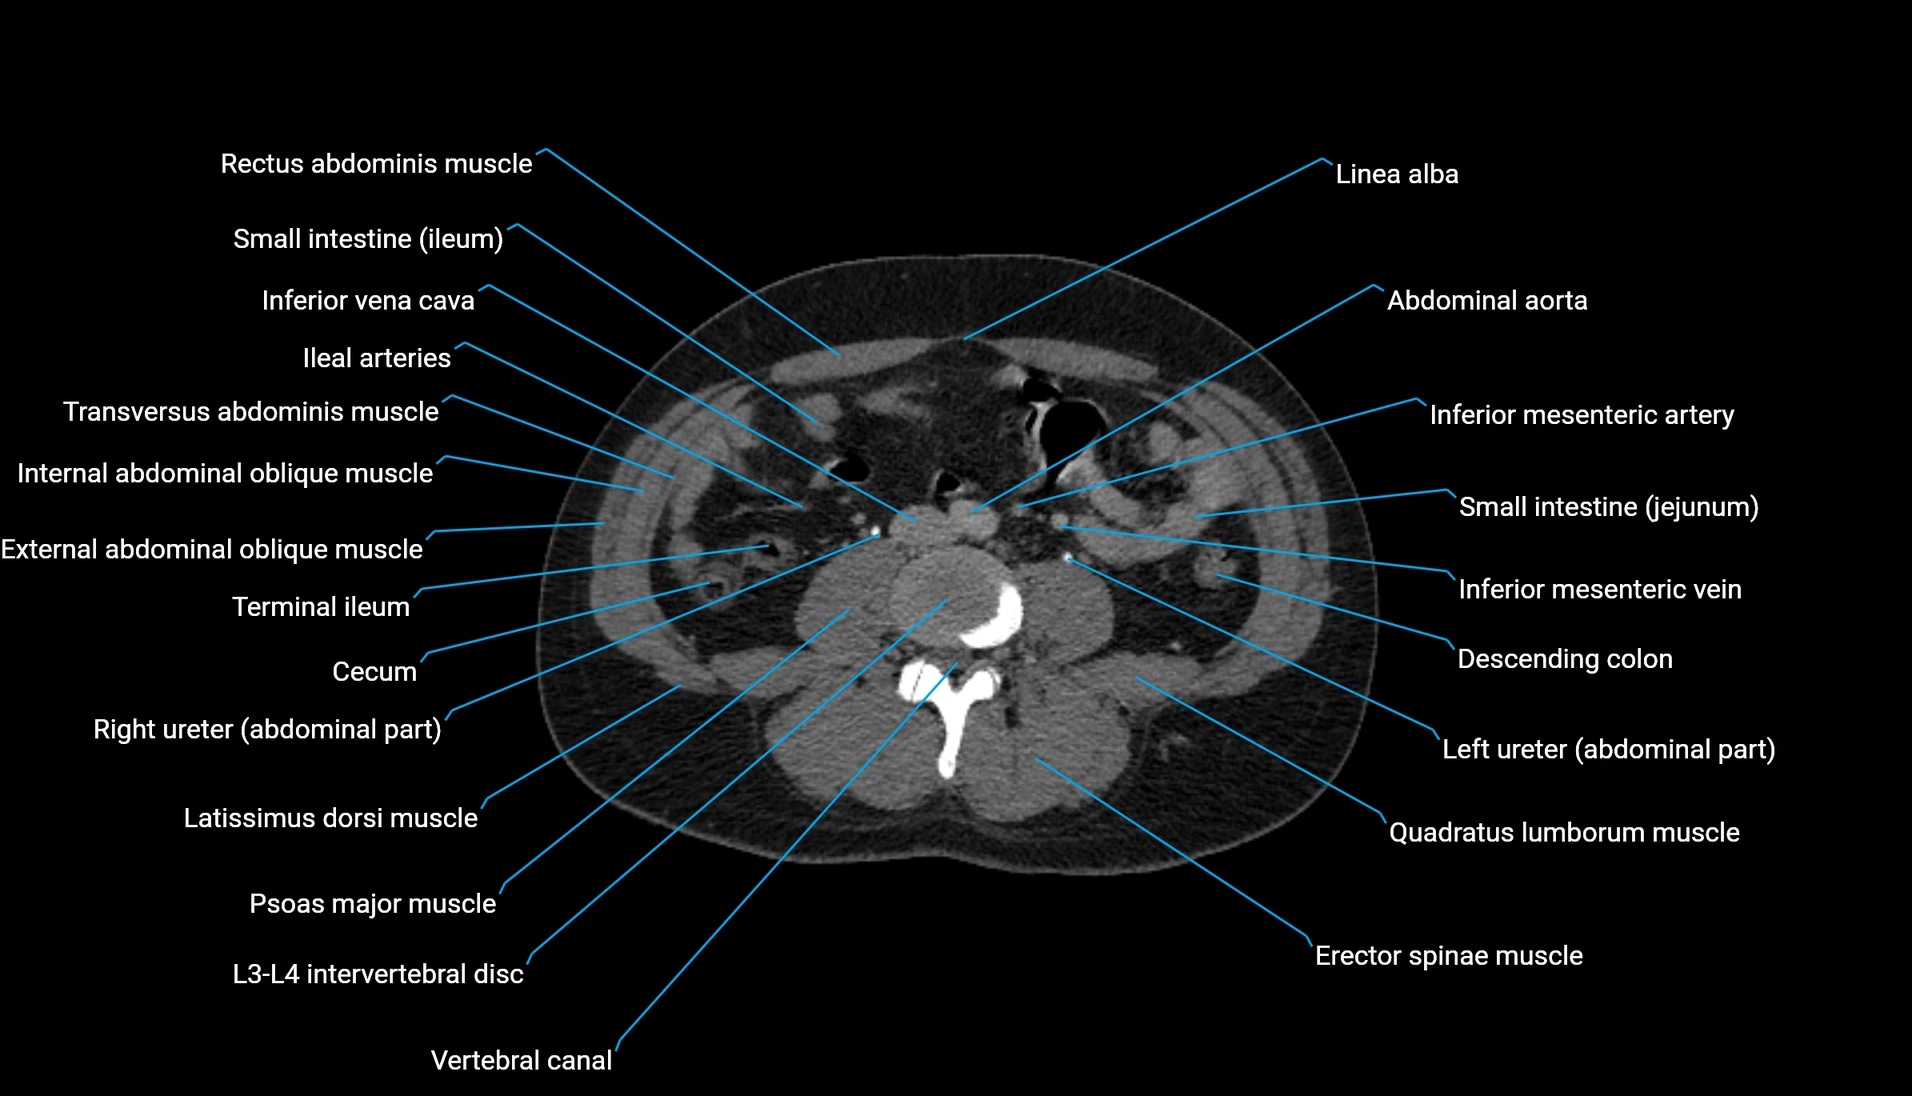

CT Appearance

Non-contrast CT:

-

Demonstrates cortical bone of acetabular rim in excellent detail

Detects fractures, dysplasia, retroversion, or bony overcoverage (pincer impingement)

3D reconstructions used in preoperative hip surgery planning

CT image